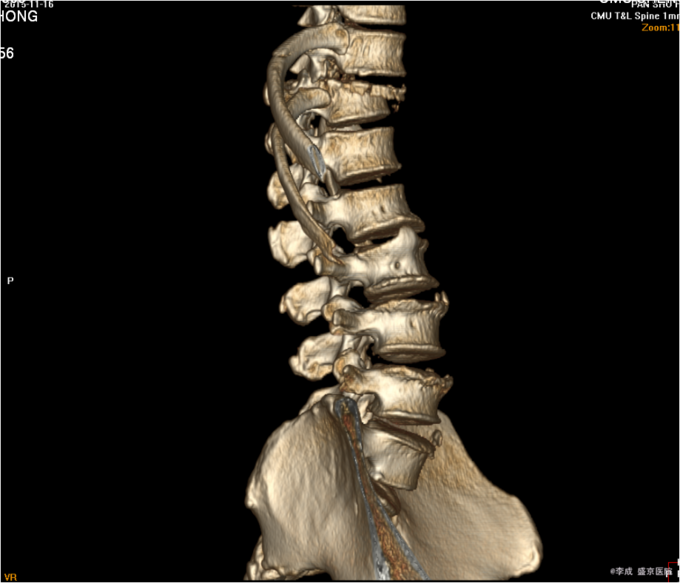

5.专科查体: 患者双上肢活动可,感觉正常 。两侧腹股沟韧带中点连线以下皮肤感觉消失。双下肢肌力均为0级,上臂肌力(R5,L5),前臂肌力(R5,L5),手掌掌屈肌力(R4,L4),手掌背伸肌力(R4,L4)。双手握力(R4,L4)。髂腰肌肌力(L0级,R0级),伸膝力(L0级,R0级),足背伸力(L0级,R0级),足跖屈肌力(L0级,R0级),神经反射:BCR:L(++)R(++),TCR:L(++)R(++),肱桡肌反射:(++)R(++),PSR: L(++++)R(++++),ASR: L(++++)R(++++),Hoffmann Sign:L(-)R(-), Babinski Sign L(-)R(-) 双侧桡动脉足背动脉可扪及搏动,末梢血运良好. 辅助检查:腰椎椎CT平扫+三维(2015-11-16,本院):胸11椎体向前滑脱,胸12椎体压缩性骨折,椎管改变,建议MR检查。 左侧第12后肋骨折。 腰1左侧横突骨折不除外。。